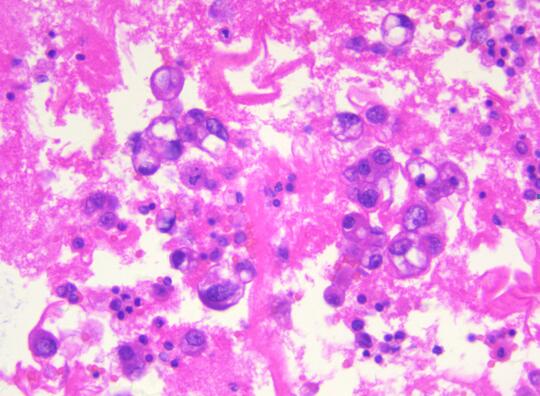

患者,女性,55岁,因腹胀不适半月余,加重乏力5天,盆腔B超提示附件包块。为了明确诊断,临床穿刺抽取500ml血性腹水做病理检查。病理科在接收到患者的腹水标本后,首先做了涂片的细胞学检查,初步提示恶性瘤细胞。在与临床大夫沟通后,科室将剩余的腹水制成了细胞蜡块,行石蜡包埋(图一)并加做了免疫细胞化学染色。免疫细胞化学结果显示Pax-8、ER、WT-1阳性(图二),同时标记间皮的指标阴性。因此,通过细胞蜡块技术该患者可明确诊断为“腺癌,卵巢来源可能性大”。随后患者进行了8次化疗,病情有所缓解,无腹胀,肿瘤系列恢复正常。

细胞蜡块的制备过程经历了沉淀和多次离心,最大限度地保留了癌细胞,减少了细胞丢失,降低了漏诊率。同时,恶性肿瘤的细胞蜡块均可进一步通过免疫细胞化学法确定癌细胞是肺来源、胃肠道来源、乳腺来源、卵巢来源、间皮来源还是淋巴细胞来源。再次,细胞蜡块切片更接近组织学,图像背景清晰,易于镜下观察,大大提高了阳性检出率。最后,细胞蜡块制作程序简单,成本不高,最重要的是细胞蜡块可连续切片进行分子检测,为精准诊断和临床个体化用药提供参考依据。该技术的成功应用大大提高了浆膜腔积液细胞诊断的阳性率,弥补了传统细胞学检查存在的一些缺陷,提高细胞病理诊断在临床的认可度。推动该技术的广泛应用,将对乐鱼在线登录入口精准细胞学诊断提供强有力的保障。